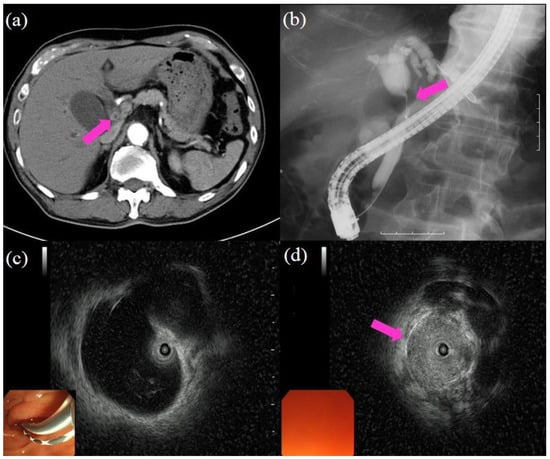

Table 4 provides the data on the diagnostic yield of pCLE for biliary strictures [58,64,65,66,67,68]. The sensitivity for malignancy is in the range of 83–98%, the specificity is 33–93%, and the accuracy is 78–93%. In a systematic review and meta-analysis of the diagnostic yield of pCLE, the pooled sensitivity and specificity for diagnosing malignancy were 90% (95% CI (84–94%)) and 75% (95% CI (66–83%)), respectively [69]. Figure 5 highlights the procedure of pCLE under direct view with POCS to diagnose biliary strictures. pCLE has been shown to have high-performance characteristics in the evaluation of biliary strictures, possibly reducing the need for repeat procedures, thereby decreasing cost. However, CLE requires additional training for interpretation. This variability of interpretation is considered to be the greatest obstacle to the widespread use of CLE.

Figure 5.

Procedure of probe-based confocal laser endomicroscopy (pCLE) under direct view with peroral cholangioscopy (POCS) to diagnose biliary strictures: (a) cholangiography showing the biliary stricture in the hilar bile duct (pink arrow); (b) POCS showing irregular thick tortuous vessels at the stricture, suggestive of malignancy; (c,d) pCLE under direct view with POCS showing dark clumps, suggestive of malignancy; the histological examination demonstrated adenocarcinoma.